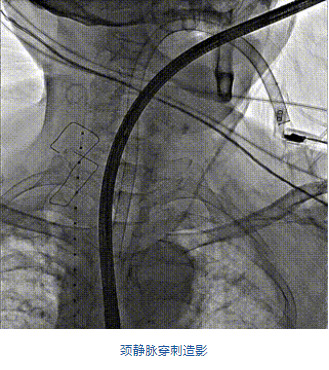

團(tuán)隊(duì)前期經(jīng)過多次討論,制定了周密的手術(shù)策略和預(yù)案。由于患者已是近九旬的超高齡老人,傳統(tǒng)外科開胸手術(shù)風(fēng)險極高,純介入經(jīng)血管三尖瓣替換能夠明顯減少創(chuàng)傷。術(shù)中陳茂及馮沅教授結(jié)合體表定位在造影指示下精準(zhǔn)穿刺右側(cè)頸靜脈并預(yù)置兩把血管縫合器。成功建立經(jīng)皮血管入路后在食道超聲和DSA的引導(dǎo)下順利完成人工瓣膜植入,術(shù)后超聲和造影顯示人工三尖瓣同軸性良好,瓣架固定牢靠,無反流和瓣周漏,平均跨瓣壓差降為1mmHg。術(shù)畢收緊預(yù)置的血管縫合器縫線完成止血,縫合效果滿意,在手術(shù)室即刻拔除氣管插管。